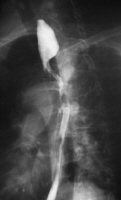

How does a barium study help you figure out whats going on in this image?

It coats the lining of the gut with barium. Smooth contrast shows normal esophagus, rough contrast shows esophageal cancer.